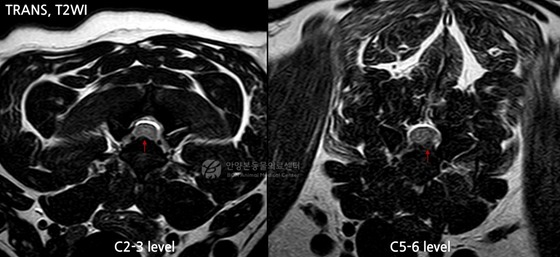

[Courtesy of Bon Animal Medical Center] To determine the cause, the medical team conducted an MRI (magnetic resonance imaging) scan. The results revealed nerve compression in the C2-3 cervical region. Notably, the C5-6 area showed severe disc herniation, severely compressing the spinal cord. The medical team identified this area as the primary cause of the acute paralysis and decided to perform immediate surgery.